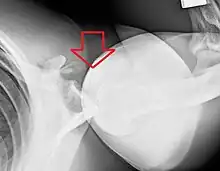

X-ray at left shows anterior dislocation in a young man. X-ray at right shows the same shoulder after reduction and internal rotation, revealing a Bankart lesion and a Hill-Sachs lesion.

In over 95% of shoulder dislocations, the humerus is displaced anteriorly.[6] In most of those, the head of the humerus comes to rest under the coracoid process, referred to as sub-coracoid dislocation. Sub-glenoid, subclavicular, and, very rarely, intrathoracic or retroperitoneal dislocations may also occur.[7]

Anterior dislocations are usually caused by a direct blow to, or fall on, an outstretched arm. The person typically holds his/her arm externally rotated and slightly abducted.

A Hill–Sachs lesion is an impaction of the head of the humerus left by the glenoid rim during dislocation.[5] Hill-Sachs deformities occur in 35–40% of anterior dislocations. They can be seen on a front-facing X-ray when the arm is in internal rotation.[8] Bankart lesions are disruptions of the glenoid labrum with or without an avulsion of bone fragment.